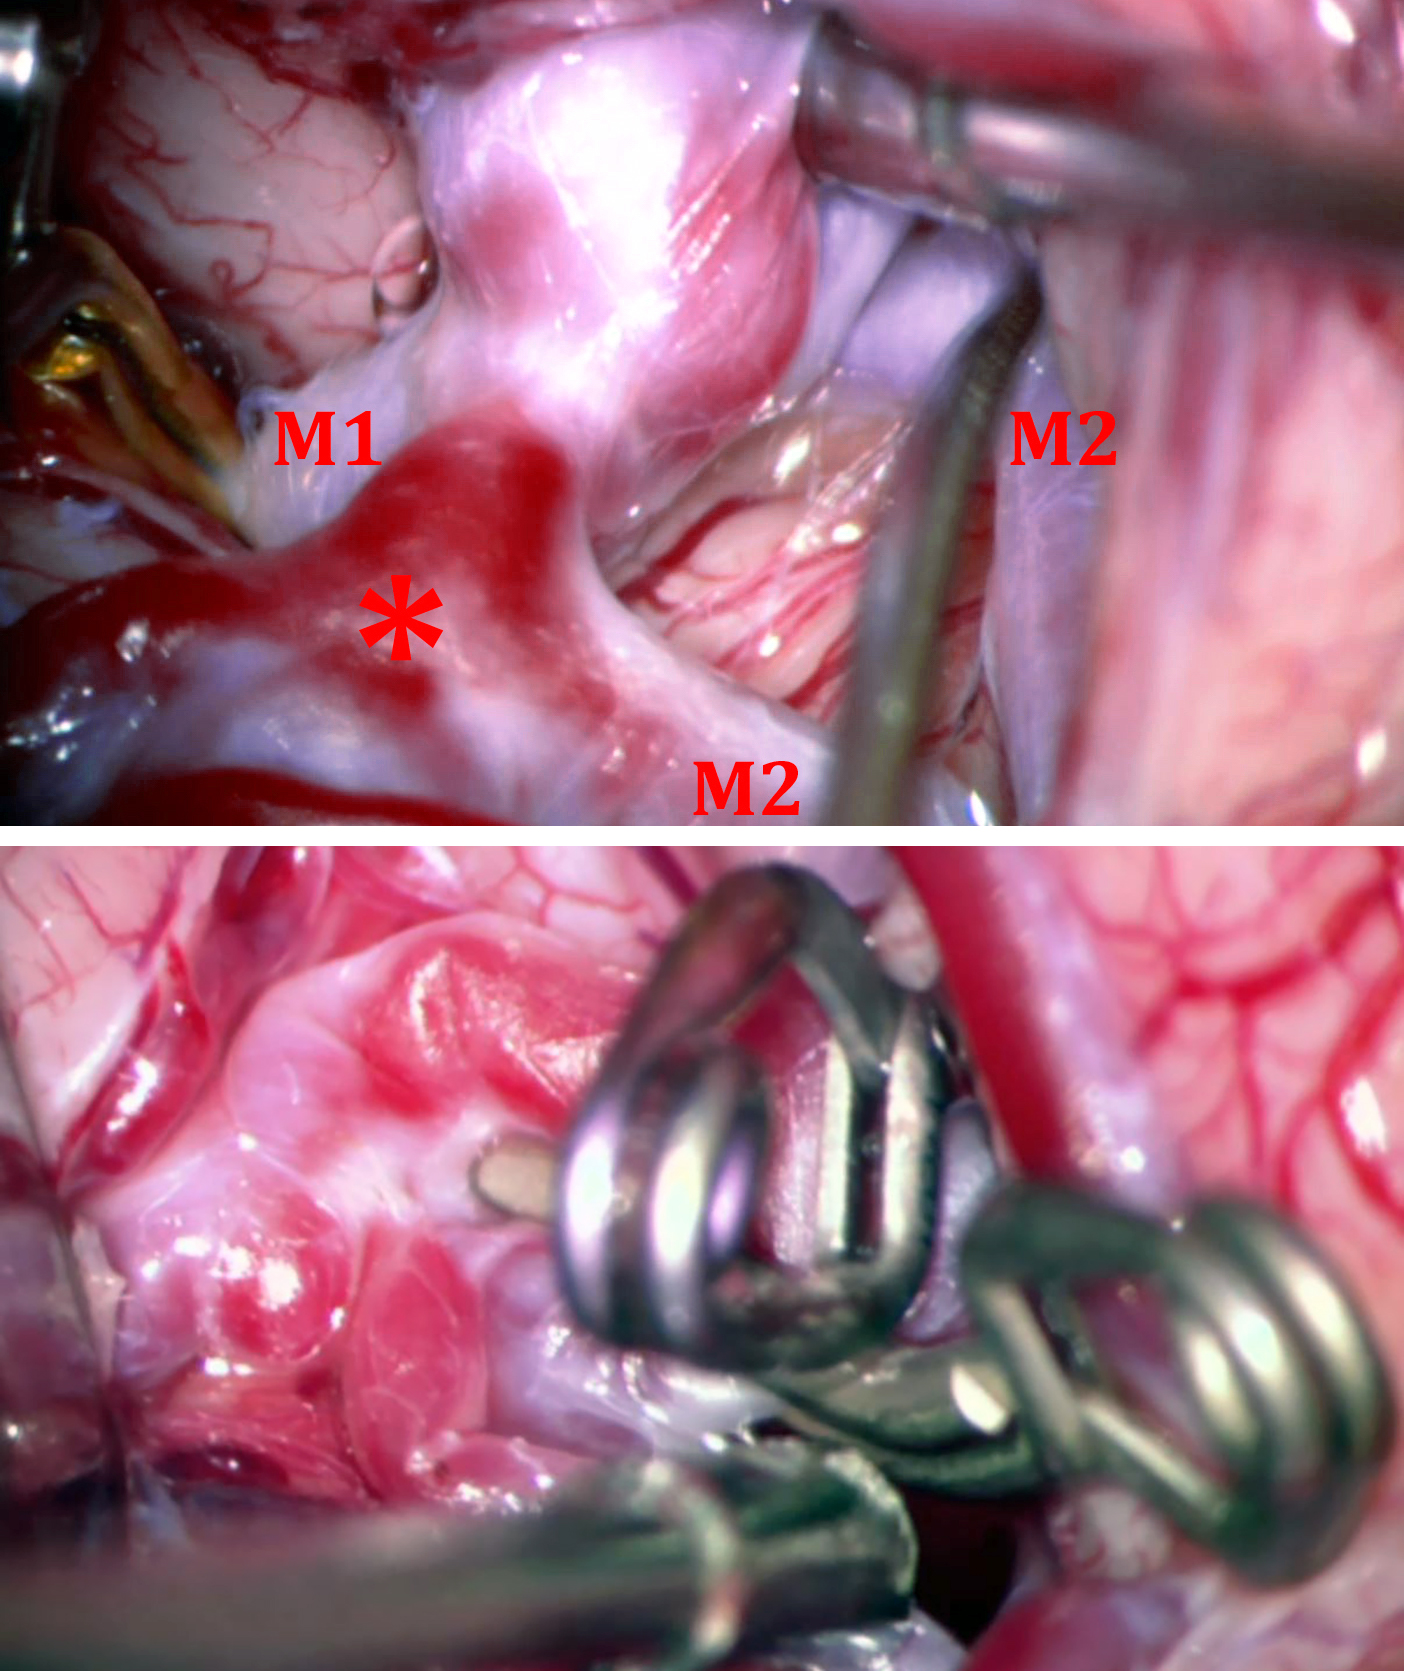

Middle Cerebral Artery Aneurysm | Cohen Collection | Volumes | The Neurosurgical Atlas